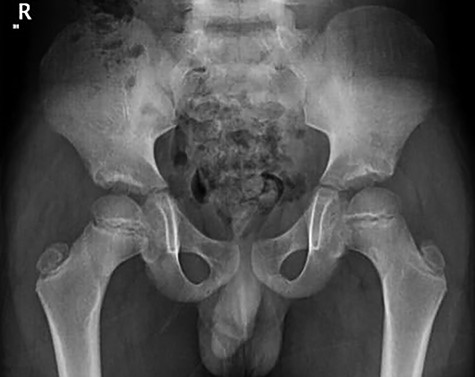

Patient was given adequate analgesia and routine blood tests were done (CRP 5.8 WBC 7.5x109). X-rays revealed small Lytic lesion with surrounding sclerosis at infero-medial aspect of left femoral neck in antero-posterior and lateral views (Fig. 1, 2).

CT hips reported a well-defined lesion seen bilaterally in the neck of femur anterior infero-medial aspect, more prominent on the left side measuring 7 x 3 mm on left side both in coronal (Fig. 3) and axial (Fig. 4) views. On the right side, other lesion measuring 2 x 1 mm (Fig. 5) seen in coronal view. These two lesions are well defined with a sclerotic border with a small cortical defect. The lesion shows fat density. The symmetrical appearance of the lesion combined with the fat density and location suggest the diagnosis of synovial herniation pit. MRI Pelvis revealed minimal left hip joint effusion with loculated fluid seen along the trochanteric bursa with the largest measuring 0.9 x 1.5 cm (Fig. 6, 7).